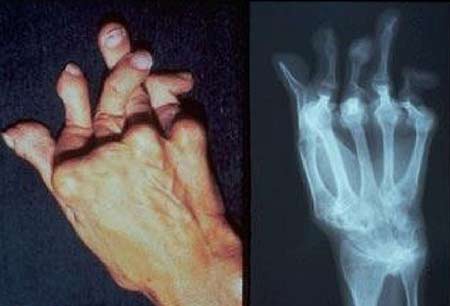

类风湿关节炎是一种对患者健康危害很大的疾病,重度时期可以致残,对于病人来说更是一个漫长甚至需要终生治疗的疾病,部分病人如若病情不加控制、用药不规范、治疗不科学可能会导致丧失工作和生活能力,甚至是影响生育。究竟类风湿性关节炎为何危害如此大?如何避免损害产生呢?本期《热线188》栏目特邀成都风湿医院马友文主任为大家详细讲解。